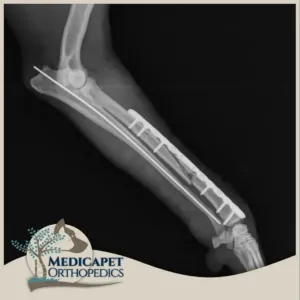

Plak Uygulamaları

Medicapet’de açık operasyon ve internal fiksasyon gerektiren kırıklarda yüksek kaliteli titanyum plaklar ve vidalar kullanıyoruz. Plak uygulamalarımızda kırık oluşan bölge eski konumuna getirildikten sonra kemiğe uygun plak tipi seçilerek bölgeye yerleştiriliyor, mümkin olan en az vidanın kullanılması ile kırığı onarıyor, gereken durumlarda iyileşmeden sonra implantı geri çıkarıyoruz. Plak uygulamalarımızdaki temel prensibimiz minimal invaziv yöntemleri kullanmaktır. Böylece mümkün olan en küçük boyuttaki kesiyi yaptığımız için iyileşme sürecini de hızlandırmış oluyoruz.